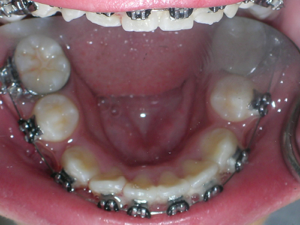

Here is what he looked like on the day that the braces were removed.

In the final photo, you can see the bonded retainer we used. A top nighttime removable retainer was made.